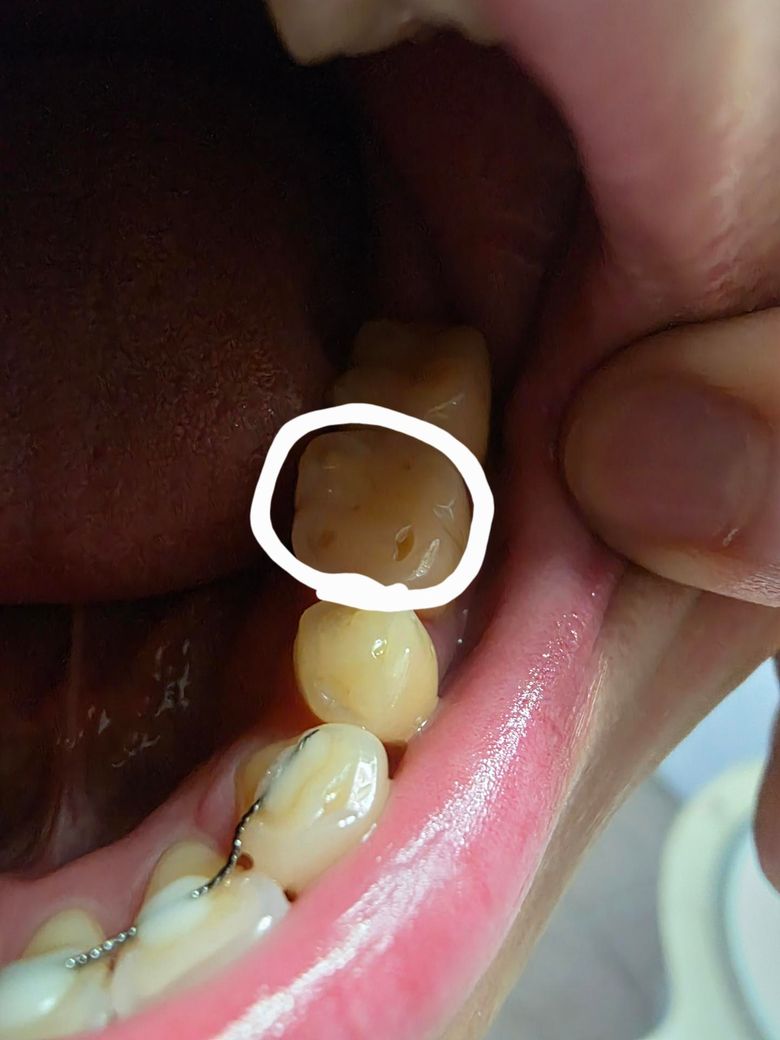

치아 단면에 구멍 난건가요?????

어금니쪽에 구멍이 난것같이 보이는데

충치인가요?? 치료가 필요한건지요??

손톱으로 만져보니 좀 패인것 같고 살짝 시린거같기도한데 통증은 없어요!

반대쪽에는 없는데 이게 뭔가요??

사진으로 봤을 경우 마모증으로 보입니다. 마모증은 치아에 과도한 힘이 가해졌을 경우 치아가 마모가 되면서 생기는 증상으로 치아에 가해지는 힘을 줄여줘야 합니다. 지속적으로 힘이 강하게 가해지게 되면 치아의 마모가 더 진행하게 되어 치아가 시리거나 불편감을 느낄 수 있습니다.

전반적으로 주변치아의 교두도 편평하고, 이갈이나 이악물기 습관으로 인해 치아가 많이 마모된 것 같습니다.

말씀하신 부위는 치아 특정부위가 패였네요

시리다면 떼워주면 될 것 같습니다

그보다는 구강 악습관이 있다면 개선하는 것이 좋을 것 같습니다